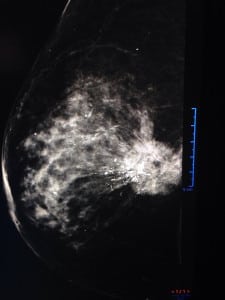

Caso 2.

Mastografía: se ve un nódulo de características sospechosas; deciden hacerle más proyecciones para ver mejor el tumor. Le hacen un ultrasonido y encuentran la sig. imagen:

Las dos proyecciones que siempre se deben hacer en una mamografía son:

- Medio lateral oblicua (se ve músculo pectoral)

- Cráneo caudal